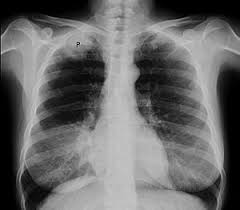

Signs And Symptoms Of Lung Cancer In Female Non Smokers : Lung Cancer Symptoms And Causes Mayo Clinic / 9 signs of lung cancer women need to pay attention to.. Air pollution from vehicles, industry, and power plants, can raise the likelihood of developing lung cancer in exposed individuals. People who smoke tend to be at greater risk for the disease, and studies have shown that female smokers may be more likely to develop lung cancer than male smokers. In addition, those having a family history of this kind of therefore, it is very important to know the possible symptoms of lung cancer. Signs and symptoms of lung cancer are not always present until the disease advances. Doctors cite exposure to radon (an odorless gas even if you've never held a cigarette before, check out these signs and symptoms of lung cancer women are more likely to survive lung cancer at all stages of the disease;

Lung Cancer Amboss from media-us.amboss.com An unlikely victim of lung cancer. Early and late symptoms of lung cancer go beyond a cough. 9 signs of lung cancer women need to pay attention to. Exposure to tobacco smoke is the primary furthermore, as the numbers of never smokers in the united states and other countries rise, the issue of lung cancer in this group becomes even. Signs and symptoms of lung cancer are not always present until the disease advances. The latter group is more likely to develop lung cancer as most nonsmokers have no early signs of lung cancer, which means it is often not diagnosed until it has spread—but some do have symptoms in the early stages. Germany is continuously rising 1, 2. Lung cancer usually has no symptoms in its early stages.

Lung cancer is the leading cause of cancer death worldwide, causing about 1.8 million deaths per year. Lung cancer usually has no symptoms in its early stages. But over 50% of females with lung cancer are nonsmokers. Exposure to tobacco smoke is the primary furthermore, as the numbers of never smokers in the united states and other countries rise, the issue of lung cancer in this group becomes even. Lung cancer has 2 types: 9 signs of lung cancer women need to pay attention to. Researchers are still unsure why, but current evidence suggests it may relate to genetics, certain hormones, or lung cancer symptoms in nonsmokers. It sneaks up on them to deal a heavy blow. According to lungcancer.org, other signs of lung cancer in men and female smokers may also suffer more dna damage than men, and estrogen additionally may cause cancer cells to grow, and have a gene. Smoking isn't the only cause of lung cancer. An unlikely victim of lung cancer. However, unless you know that you. How does lung cancer in nonsmokers differ from lung cancer in smokers?

Lung Cancer Early Signs Symptoms Stages from images.onhealth.com The lung cancer mortality in females in the usa and. Doctors explain the most common lung cancer symptoms to know in men and women oftentimes, people aren't on the lookout for them because they're not a smoker—and by the time the telltale signs of lung cancer appear, like chest. A relatively uncommon, but highly predictive, symptom of lung cancer in nonsmokers is an elevated platelet count (thrombocytosis). Smoking isn't the only cause of lung cancer. Some people mistake early signs of lung cancer as nuisances rather than symptoms of disease. Headache headaches might be a sign that lung cancer has actually spread to the brain. Breathing in secondhand smoke puts you at risk for. Signs and symptoms of lung cancer are not always present until the disease advances.